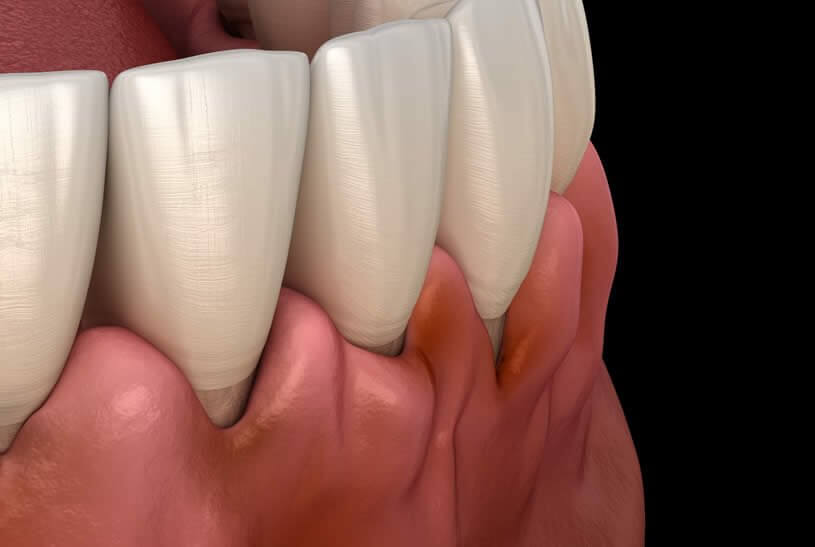

PERIODONTITIS & GINGIVAL RETRACTION

Periodontitis, also known as gingival recession or gum disease, is a very severe gum infection that damages the soft tissue around the teeth and, if left untreated, causes melting of the bone that supports the teeth of the patients.

- Periodontal problems are bacterial gum infections of the gum tissue and the bone holding the teeth. Gum disease is the main cause of gum recession.

- Crowded teeth or a misaligned set of teeth cause gingival recession as a result of excessive traumatic forces.